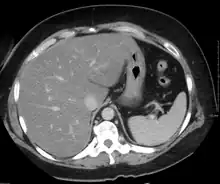

Medical imaging

On X-ray computed tomography (CT), the increased fat component will decrease the density of the liver tissue, making the image less bright. Typically the density of the spleen and liver are roughly equivalent. In steatosis, there is a difference between the density and brightness of the two organs, with the liver appearing darker.[12] On ultrasound, fat is more echogenic (capable of reflecting sound waves). The combination of liver steatosis being dark on CT and bright on ultrasound is sometimes known as the flip flop sign.

On magnetic resonance imaging, multiecho gradient echo images can be used to determine the percent fat fraction of the liver.[13] The different resonance frequencies between water and fat make this technique very sensitive and accurate. Acquisition of echoes in "in phase" and "out phase" conditions (pertaining to the relative phases of the fat and water proton contingents) enables to obtain a signal proportional to the water and fat contingent, or a signal proportional to the water minus the fat contingent. These signal intensities are then algebraically combined into a percent fat. More recent techniques take into account experimental noise, signal decay and spectroscopic properties of fat. Numerous validation studies have demonstrated excellent correlations between the steatosis level quantified at MRI and the steatosis levels semi-quantitatively and quantitatively determined on liver biopsies (reference methods). Several MRI vendors offer automated calculation of percent fat with acquisition sequences no longer than a single breath hold.